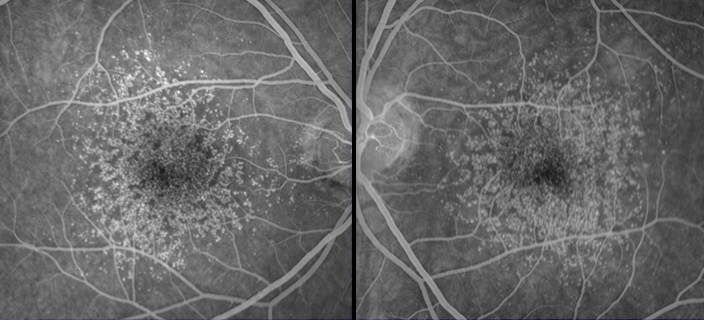

Archives of Ophthalmology Paper on Idiopathic Macular Telangiectasia, Type 1

Macula Foundation investigators re-classified Idiopathic Macular Telangiectasia Type 1 and Type 2 in an updated version based on its clinical characteristics and angiographic features.

Idiopathic macular telangiectasia. Arch Ophthalmol 124:450-460, April 2006.

Expanded Clinical Spectrum of Idiopathic Macular Telangiectasia Type 2

Brue C, Tseng J, Barbazetto I, Lima L, Yannuzzi L.

Peculiar manifestation of macular telangiectasia type 2. Retin Cases Brief Rep 5(4):309-312, 2011.